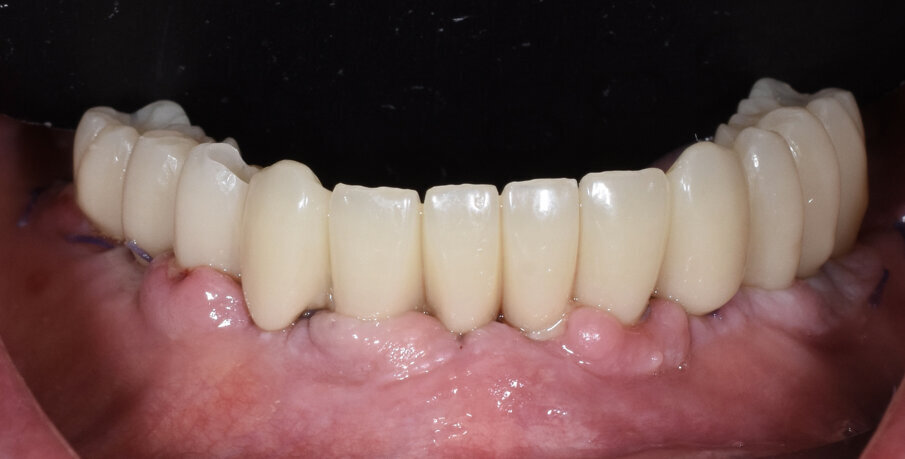

Paziente di sesso maschile di 73 anni, con anamnesi negativa per patologie di rilievo. All’esame clinico e radiografico si evidenzia nell’arcata inferiore la presenza di residui radicolari a supporto di un vecchio ponte, con attacchi per la stabilizzazione di una protesi scheletrata di tipo mobile. Prima di procedere alla fase chirurgica e di rimuovere lo scheletrito viene eseguita un impronta digitale con scanner (3Shape) in modo da registrare la dimensione verticale che verrà utilizzata come riferimento per la realizzazione del carico immediato. In sedazione cosciente e previa terapia antibiotica si procede alla rimozione dei residui radicolari, quindi si esegue una generosa osteotomia e si procede al posizionamento di numero 6 impianti assiali (AB Dental device) a esagono interno. Si esegue quindi la sutura dei lembi con vicryl 4/0 e si procede alla prese dell’impronta digitale utilizzando gli scan body come transfer (Figg. 1-11). I file in STL vengono inviati al laboratorio per la realizzazione della protesi provvisoria a carico immediato. Si applicano quindi le viti di guarigione. Dopo 72 ore si procede alla consegna del provvisorio che rimarrà in bocca per 4 mesi in attesa dell’osteointegrazione (Figg. 12-23).

Fig. 17 - Visione occlusale del provvisorio.

Fig. 18 - Dettagli del provvisorio.

Fig. 20 - Visione occlusale provvisorio.

Fig. 21 - Carico immediato.

Fig. 22 - Visione occlusale carico immediato.